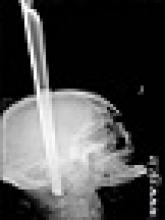

این مرد که نامش فاش نشده است پس از حادثه بی هوش شده و سریعا به بیمارستان انتقال یافت و در آنجا پزشکان توانستند پس از یک عمل جراحی 4 ساعته این میله را از سر فرد مصدوم خارج کنند. این درحالی است که با کمال خوش شانسی میله از کنار مغزش رد شده و به دندان هایش رسیده است.

پزشکان اعلام کرده اند که این مرد 40 ساله تقریبا شانسی برابر با صفر برای زنده ماندن داشت اما حالا پس از یک عمل سخت کاملا بهبود یافته است و تا چند هفته دیگر نیز از بیمارستان مرخص خواهد شد. این اتفاقات روزانه به دفعات در دنیا رخ می دهد اما کمتر کسی از آن جان سالم به در می برد.